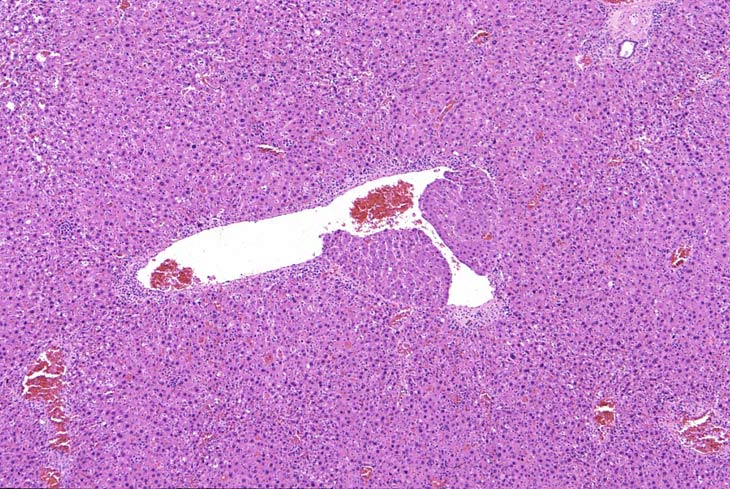

In some foci of cellular alteration, primarily basophilic foci, hepatocytes may occasional be seen to protrude into the lumen of hepatic veins. They are usually lined by a layer of flattened endothelial cells. This change has been considered by some to represent a form of microinvasion and such lesions have been diagnosed as hepatocellular carcinomas, possibly motivated by the fact that most are seen within foci induced by treatment with hepatocarcinogens. However, similar changes are occasionally seen in untreated mice and may not necessarily be associated with a focus of cellular alteration. Consequently, we cannot be certain that this change is actually a microcarcinoma. Two clusters of hepatocytes protruding into a large hepatic vein.